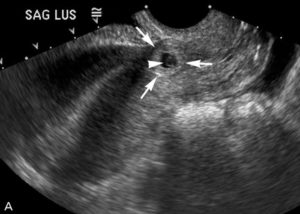

Видно на УЗД на ранніх термінах, як візуалізується

За допомогою УЗД дослідження патологія виявляється за ознаками:

- всередині порожнини матки плідного яйця немає;

- матка не збільшена;

- на одному з придатків спостерігається утворення;

- рідина позаду матки (при розриві труби).